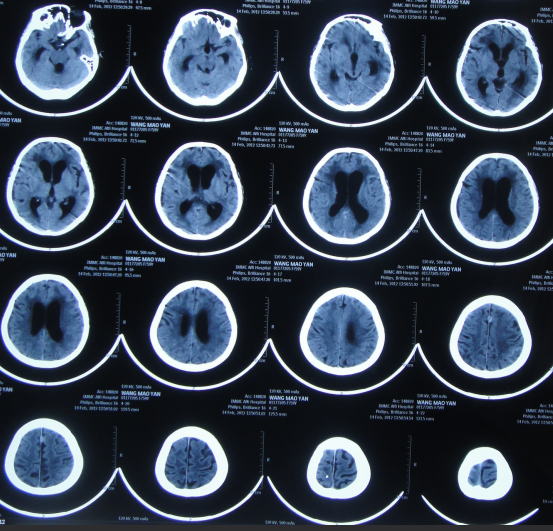

第2家医院出院1月余即2012年2月7日,夜里起夜突然又重复发作以前的症状(恶心呕吐、头昏),且比前2次发作严重,2012年2月8日住入第3家医院:呼和浩特市某三甲医院的神经外科治疗,入院查头颅CT(图-2)和MRI(图-3);脊髓核磁(图-4);肺部CT(图-5)及多次腰椎穿刺脑脊液化验检查(糖低、蛋白高),诊断为:结核性脑膜炎,脑积水。

图-2:2012年2月9日头颅CT